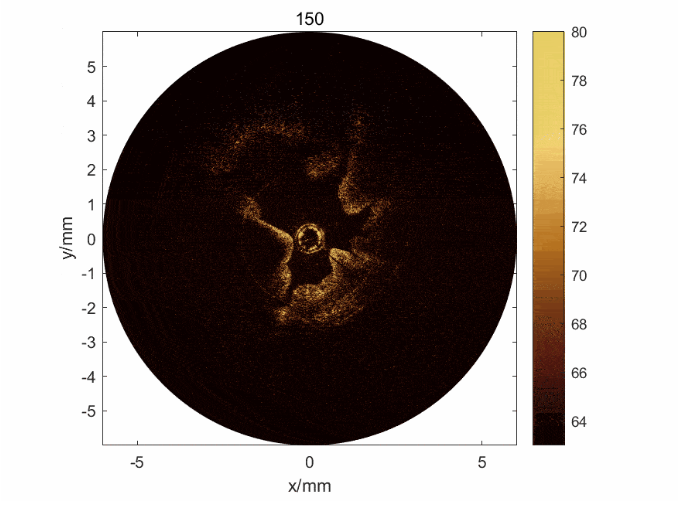

圖2: a) 子宮內(nèi)膜損傷模型兔的OCT/超聲圖像及其圖像分割和量化方法; b) 通過雙模態(tài)獲取的信息可以判斷子宮內(nèi)膜的損傷程度,驗(yàn)證了雙模態(tài)的必要性